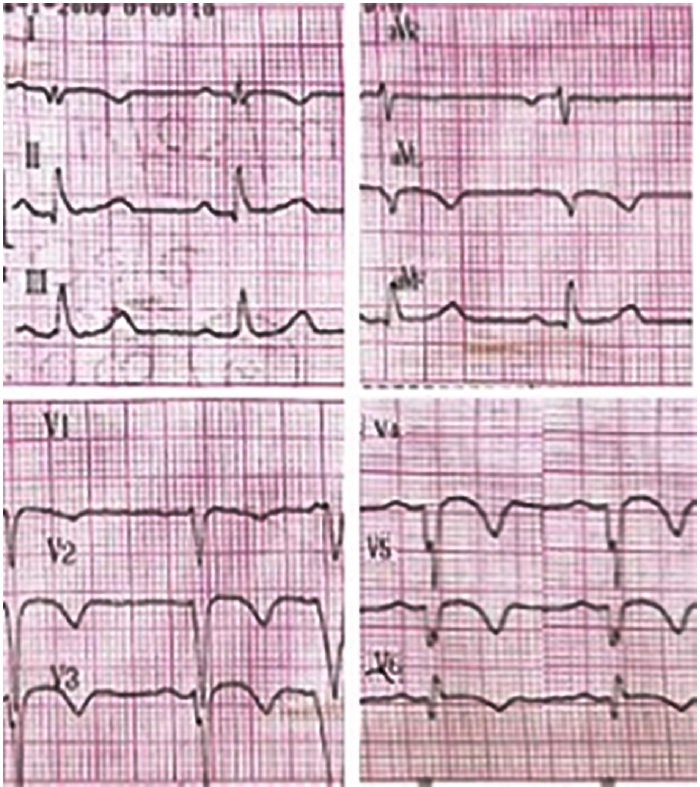

We present the case of a 30-year-old male patient with history of non-atherosclerotic dilated ischemicnecrotic cardiomyopathy, with reduced left ventricular ejection fraction (LVEF) (35%) and ventricular aneurysm (Figure 1), as a result of extrinsic iatrogenic lesion following anterior descending artery suture due to gunshot wound and urgent surgery. He subsequently underwent various hospitalizations for recurrent sustained monomorphic ventricular tachycardia (SMVT) (Figure 2a), leading to implantable cardioverter defibrillator (ICD) placement and substrate ablation, with favorable outcome.

Fig. 2b Electrocardiogram after electrical cardioversion showing sinus rhythm at 65 bpm, with presence of negative Q and T waves in the anterolateral wall, compatible with necrosis sequel and repolarization disorders.